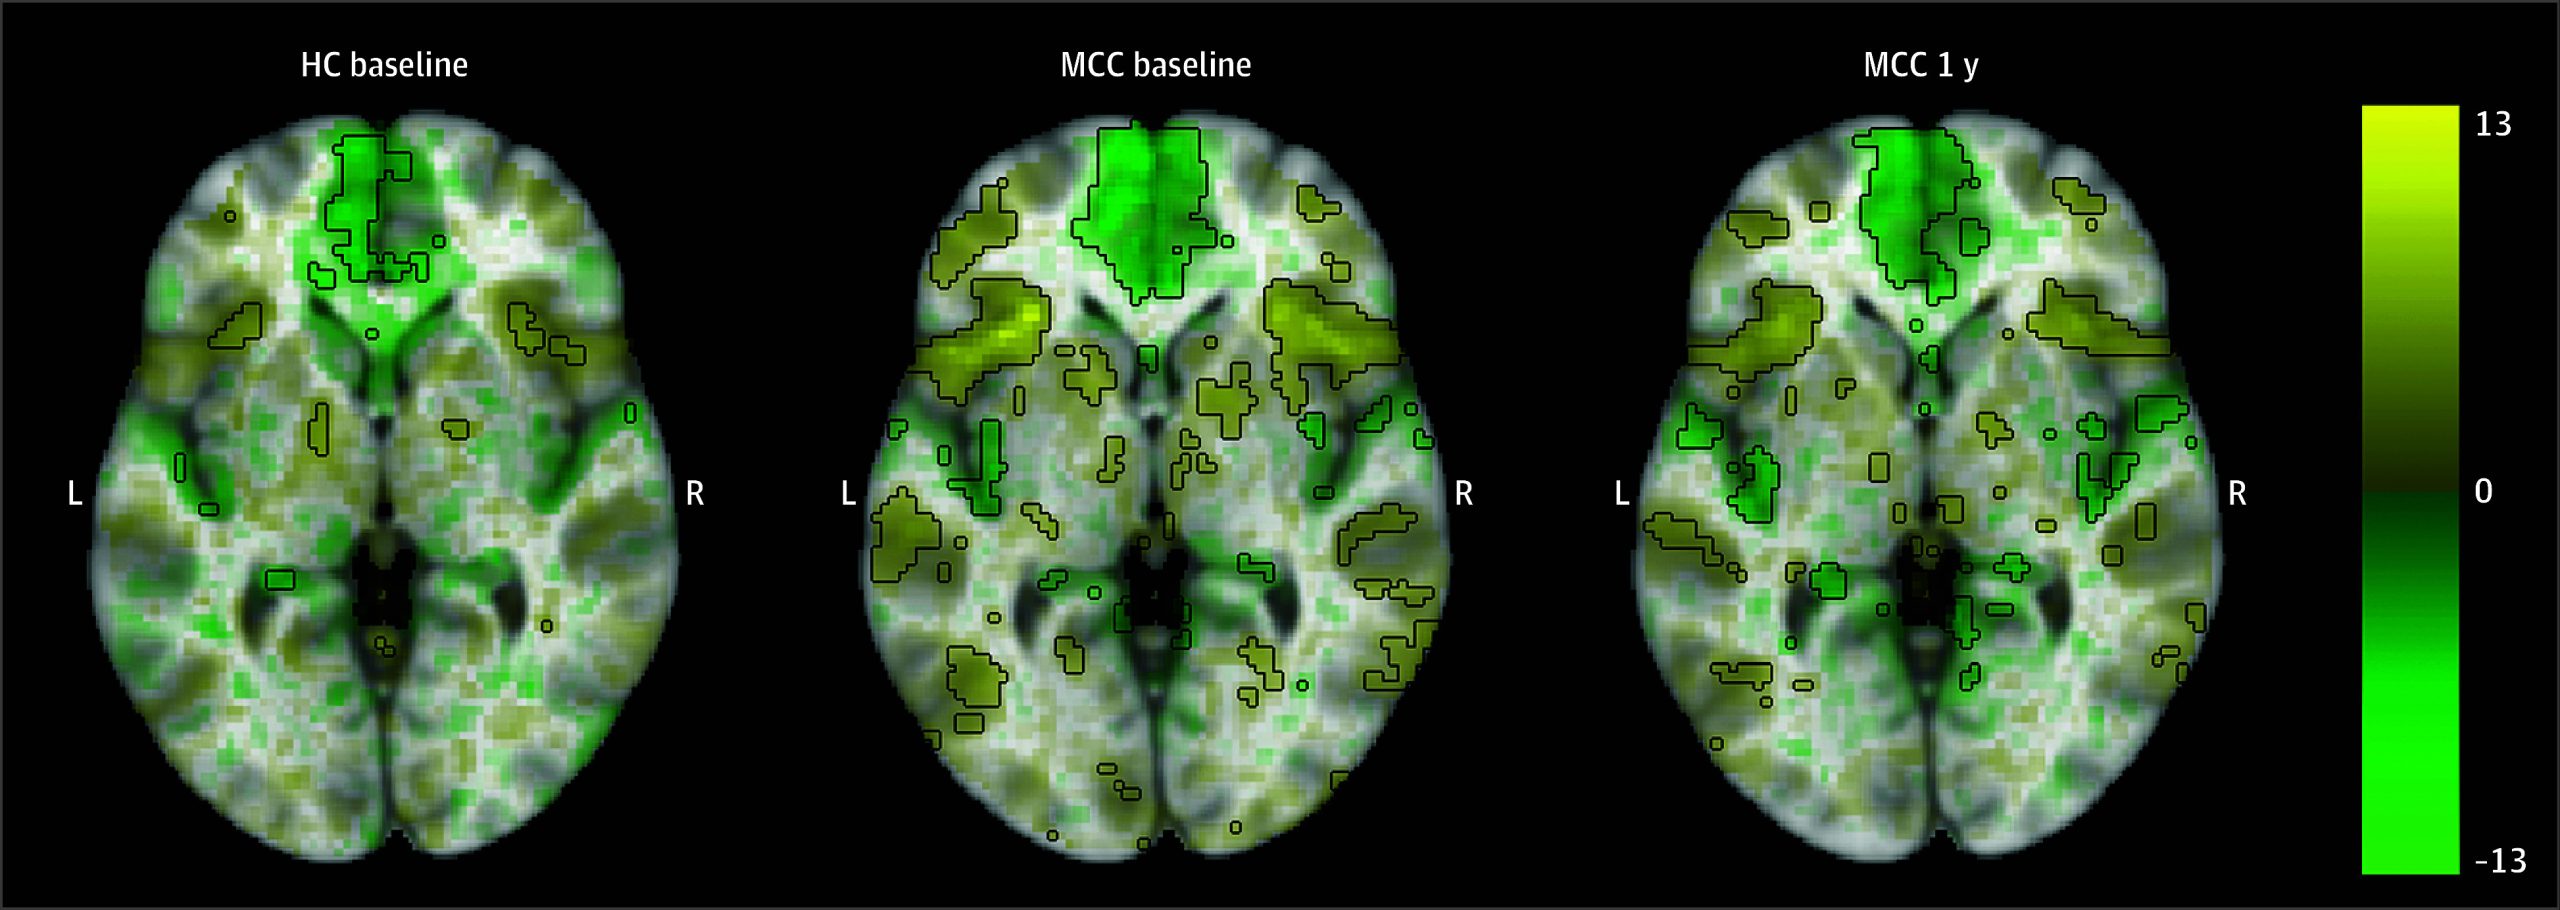

Activation in prefrontal and parietal cortical regions was observed for the 2-back vs 0-back image contrast in all groups, including MCC participants at baseline and 1 year as well as control participants (Figure 1; eAppendix 1 and eFigure 5 in Supplement 1). There were no significant differences in activation between the groups at baseline (22 HC participants and 40 MCC participants) or between the 2 time points of the MCC group (25 participants), and no associations between cannabis use frequency change and activation at 1 year for the MCC group were significant.